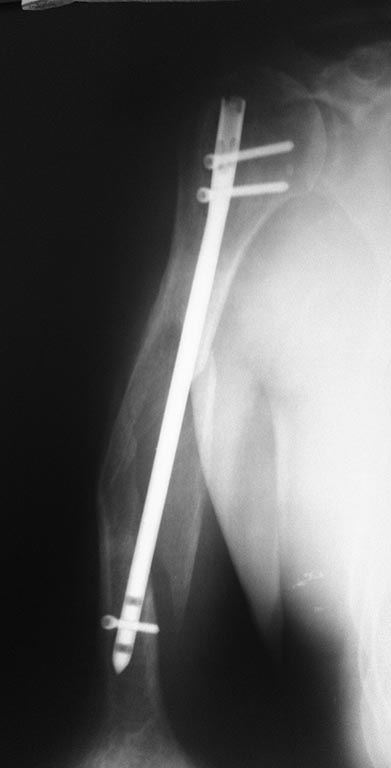

[Ortho] Ложный сустав плеча после БИОС

Мужчина, 57 лет, плотного телосложения. Тяжелых сопутствующих нет.

Оперирован в ноябре 2014 года. В настоящий момент сохраняется

патологическая подвижность. Честно говоря, пациента это не сильно

беспокоит (не без труда уговорил его прийти на след. неделе). Есть в

наличии штифты, пластины и аппарат при необходимости соберем. Заранее

благодарен!